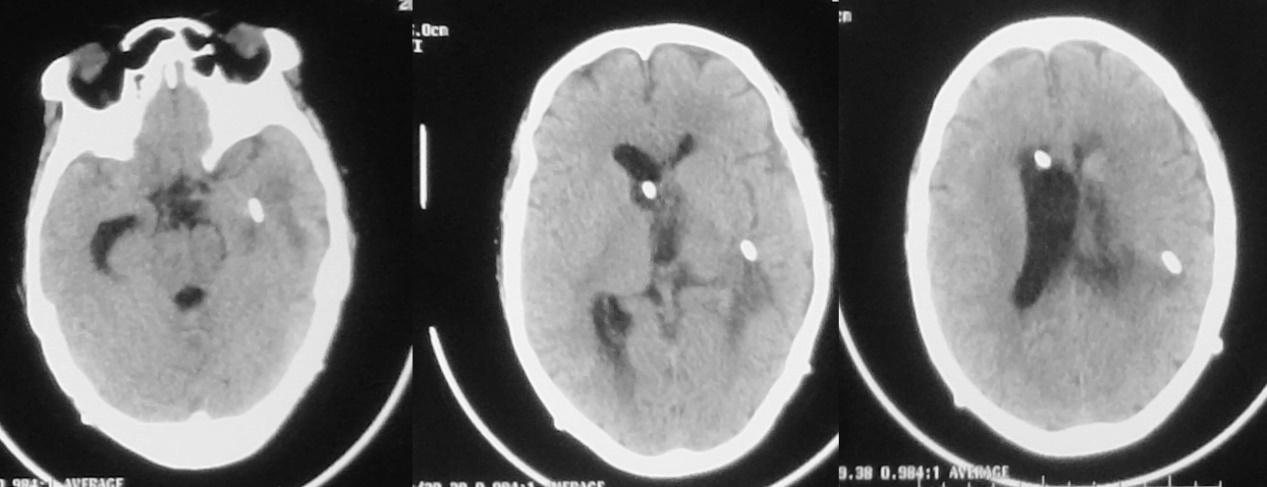

脓肿清除术后第3天,颞角外引流术后第2天即2020年12月10日,意识仍呈朦胧状态,刺激睁眼,简单配合动作,复查头颅CT呈术后改变,但右侧脑室 较前明显扩张( 图-12); 当天行加行右侧脑室穿刺外引流术。

图-12: 2020年12月10日头CT

脓肿清除术后第5天,颞角外引流术后第4天,右侧脑室穿刺术后2天,即2020年12月12日上午,意识进一步变差,呈浅昏迷状态,复查头颅CT( 图-13 )见脑室缩小,但术区水肿明显;当天下午意识又有恶化,再次复查头颅CT( 图-14 )见术区水肿明显加重,转入ICU进一步治疗,并于当天进行了气管切开术。

图-13: 2020年12月12日上午头CT

图-14: 2020年12月12日下午头CT

脓肿清除术后第8天,左侧颞角外引流术后第7天,右侧脑室穿刺术后5天,即2020年12月16日复查头颅CT见术区出血开始吸收,但水肿仍明显,脑室无扩张( 图-15 )。

图-15: 2020年12月16日头CT

患者体温正常,仍呈朦胧状态,可自动睁眼,刺激肢体可活动。脓肿清除术后第13天,左侧颞角外引流术后第12天,右侧脑室穿刺术后10天,即2020年12月21日,复查头颅核磁( 图-16 )见脑室缩小,丘脑脓肿病灶缩小,左侧脑室枕角和小脑表面的强化灶消失,提示颅内感染好转。

图-16: 2020年12月21日头增强核磁